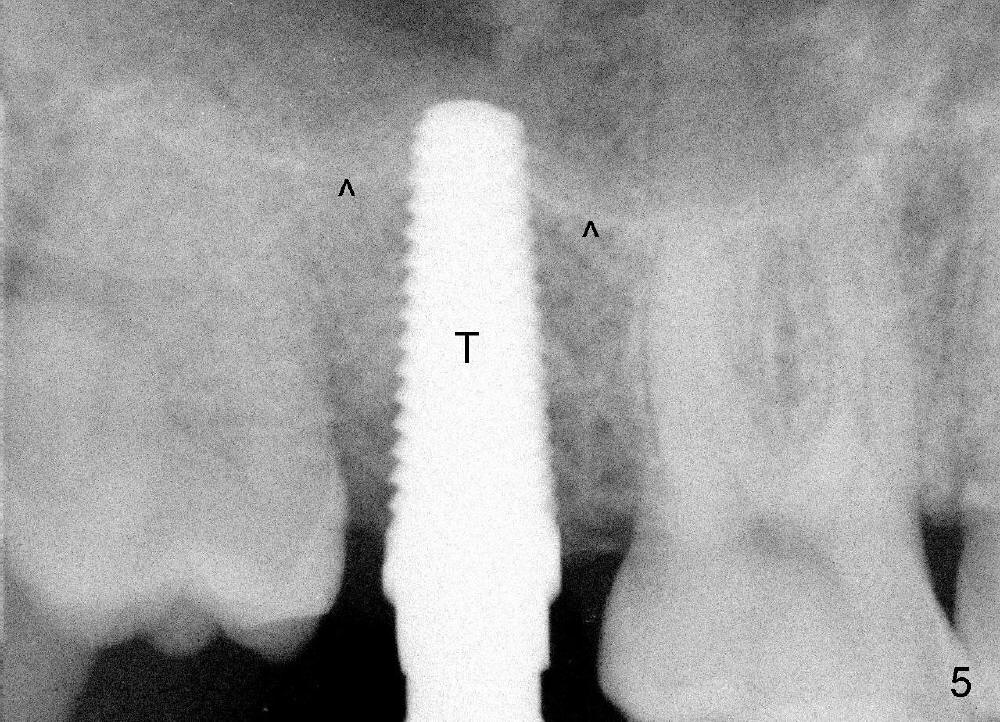

A 42-year-old man is afraid of dentistry. Residual roots of #2 remain untreated for at least 2.5 years (Fig.1). Both the mesiodistal space and the height are limited and unfavorable to restoration (Fig.2,3). Finally he agrees to have treatment, since the tooth #15 is worn so much that it is sensitive to mastication. When the tooth #2 is extracted, the socket is triangular without septum (Fig.4); the bottom of the socket is flat and easy for osteotomy. A 5x17 mm tap has obtained stability once it is placed ~ 14 mm deep (Fig.5). A 5x14 mm implant is placed with insertion torque > 60 Ncm (Fig.6 I), followed by placement of 4x3 mm abutment (A).